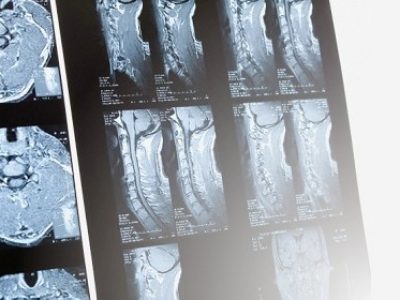

Health Blogs Common Symptoms Foot Pain Read More → Headache Read More → Limb Numbness Read More → Common Conditions Osteoporosis Read More → Arthritis Read More → Pinched Nerve Read More → Spine and Joint Health Tips Video One standing Abs exercise lose belly fat Read More → Exercises to improve Diastasis recti Read More → Elders five strengthening exercises prevent falling Read More → Case Sharing Fibromyalgia Read More → Blurred Vision, Brain Tumor Warning Sign? Read More → Understanding MRI and X ray to view herniated disc Read More →